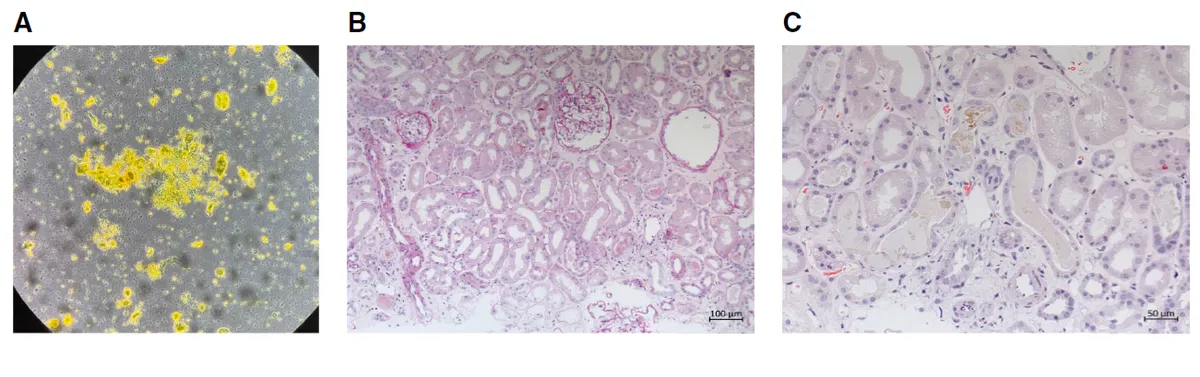

**Figura 1.** Achados urinários e histológicos da biópsia renal. (A) O sedimento urinário mostra células epiteliais tubulares, cilindros granulares corados por bile e cristais de leucina. (B) Os túbulos renais apresentam células epiteliais achatadas e perda da borda em escova (NTA). (C) Os túbulos exibem cilindros amarelo-esverdeados corados por bile (H&E).

O sedimento urinário revelou cilindro biliares, cristais de leucina e células tubulares — achados que direcionam o raciocínio para lesão tubular por pigmentos.

Foi realizado biópsia confirmando existência de necrose tubular aguda com cilindros biliares, compatível com Nefropatia Colêmica.